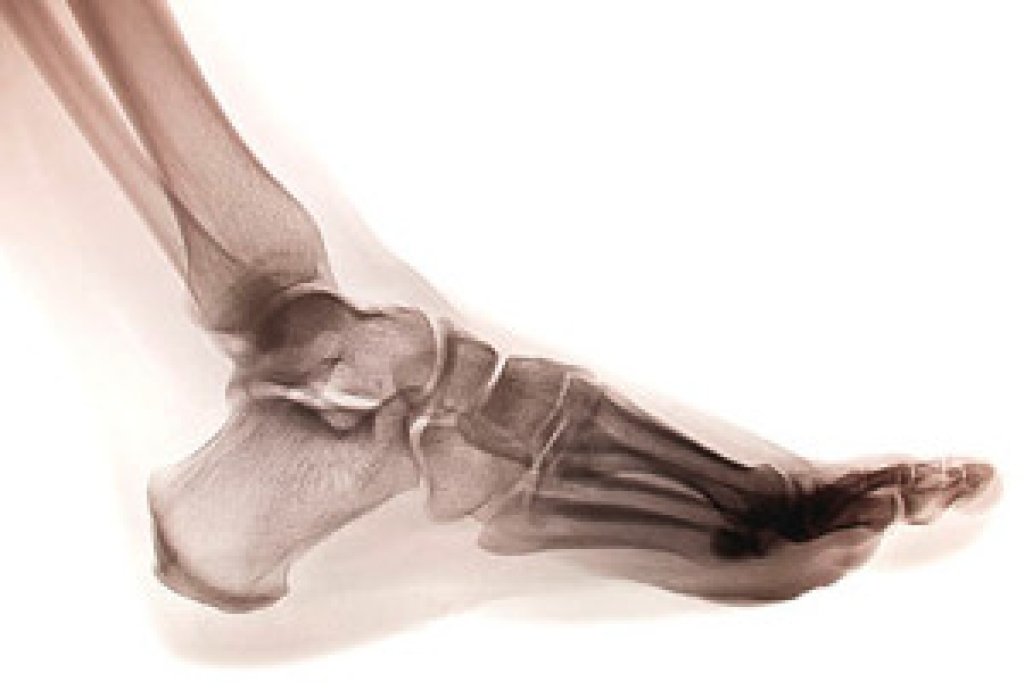

Many runners end up with heel spurs, often as the result of repetitive pounding on hard surfaces. A heel spur, also known as a calcaneal spur, is a bony protrusion on the underside of the calcaneus bone of the heel. Plantar fasciitis sometimes damages the membrane that covers the heel bone, making it more likely for heel spurs to form. Although heel spurs can become quite painful, many people develop them over time without knowing it. In general, it is not a heel spur itself, but damage to its surrounding tissue that causes the pain. Common causes of heel spurs include overstretching the plantar fascia, damage to foot muscles and ligaments, and wearing shoes that lack proper cushioning or arch support. Many nonsurgical treatments successfully reduce the pain, including cortisone injections, taping, custom orthotics, exercises, and replacing footwear. If your heel pain persists, it is a good idea to consult a podiatrist for an examination, a diagnosis, and an appropriate treatment.

Heel spurs are formed by calcium deposits on the back of the foot where the heel is. This can also be caused by small fragments of bone breaking off one section of the foot, attaching onto the back of the foot. Heel spurs can also be bone growth on the back of the foot and may grow in the direction of the arch of the foot.